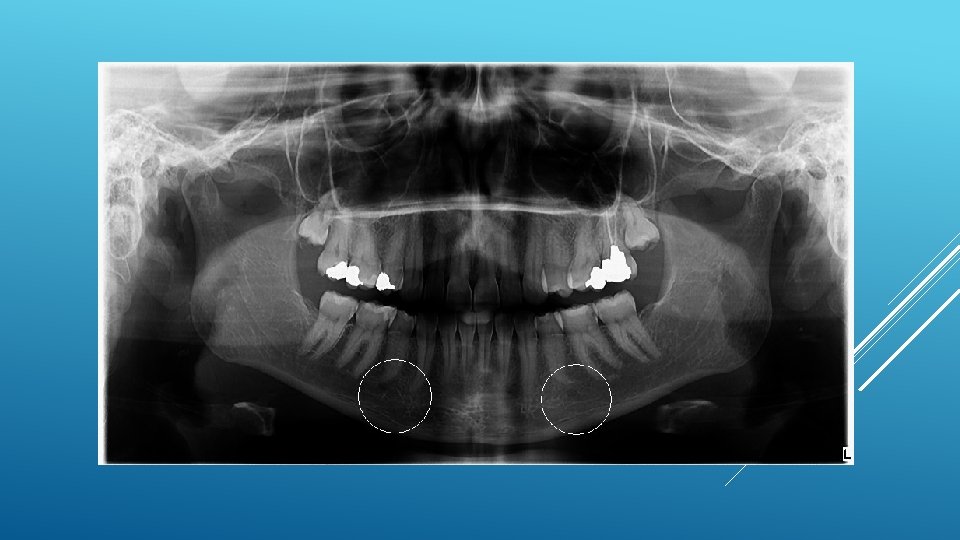

LOCATION AND DIMENSIONS OF THE MENTAL FORAMEN: A RADIOGRAPHIC ANALYSIS BY USING CONE-BEAM COMPUTED TOMOGRAPHY The majority of MF (56%) were located apically between the 2 premolars, and another 35. 7% of MF were positioned below the second premolar. On average, the MF was localized 5. 0 mm from the closest root of the adjacent tooth (range, 0. 3 -9. 8 mm). The mean size of the MF showed a height of 3. 0 mm and a length of 3. 2 mm; however, individual cases showed large differences in height (1. 8 -5. 1 mm) and in length (1. 8 -5. 5 mm). All mental canals exiting the MF demonstrated an upward course in the coronal plane, with 70. 1% of the mental canal presenting an anterior loop (AL) in the axial view. The mean extension of AL in cases with an AL was 2. 3 mm.

RELATIONSHIP BETWEEN THE POSITION OF THE MENTAL FORAMEN AND THE ANTERIOR LOOP OF THE INFERIOR ALVEOLAR NERVE AS DETERMINED BY CONE BEAM COMPUTED TOMOGRAPHY COMBINED WITH MIMICS The parameters were measured, and their values include mean (SD) anterior loop length, 1. 16 (1. 78) mm; anterior loop angle, 19. 13 (26. 89) degrees; inferior alveolar canal diameter, 3. 01 (0. 67) mm; height of the inferior alveolar canal, 10. 32 (1. 56) mm; 2 -dimensional mental foramen diameter, 2. 97 (0. 61) mm; 3 D mental foramen diameter, 2. 95 (0. 59) mm; 2 -dimensional vertical height of the mental foramen, 14. 67 (1. 67) mm; and 3 D vertical height of the mental foramen, 14. 61 (1. 69) mm. The mental foramen was located apically between the first and second premolars in 51. 67% and below the second premolar in 40. 83% of the cases.

THE MENTAL FORAMEN OR "THE CROSSROADS OF THE MANDIBLE. " AN ANATOMIC AND CLINICAL OBSERVATION] [ARTICLE IN FRENCH, GERMAN] THOMAS VON ARX 1 This paper presents a clinical and anatomical review of the mental foramen (MF) based on recent publications (since 1990). Usually, the MF is located below the 2 nd premolar or between the two premolars, but it may also be positioned below the 1 st premolar or below the mesial root of the 1 st molar. At the level of the MF, lingual canals may join the mandibular canal (hence the term "crossroads"). Accessory MF are frequently described in the literature with large ethnic variations in incidence. The emergence pattern of the mental canal usually has an upward and posterior direction. The presence and extent of an "anterior loop" of the mental canal may be overestimated with panoramic radiography. Limited cone-beam computed tomography currently appears to be the most precise radiographic technique for assessment of the "anterior loop". The mental nerve exiting the MF usually has three to four branches for innervation of the soft tissues of the chin, lower lip, facial gingiva and mucosa in the anterior mandible. The clinician is advised to observe a safety distance when performing incisions and osteotomies in the vicinity of the MF.

ANATOMICAL RELATIONSHIP BETWEEN MENTAL FORAMEN, MANDIBULAR TEETH AND RISK OF NERVE INJURY WITH ENDODONTIC TREATMENT he root apex of the mandibular second premolar (70 %), followed by the first premolar (18 %) and then the first molar (12 %), was the closest to the MF. Ninetysix percent of root apices evaluated were >3 mm from the MF. An AL was present in 88 % of the cases. Conclusions: With regards to endodontic treatment, the risk of nerve injury in the vicinity of the MF would appear to be low. However, the high incidence of the AL highlights the need for clinicians to be aware and careful of this important anatomical feature.

ASSESSMENT OF MORPHOLOGICAL AND ANATOMICAL CHARACTERISTICS OF MENTAL FORAMEN USING CONE BEAM COMPUTED TOMOGRAPHY All mental foramina were visualized. Regarding location, 49. 2% of the MFs were located between first and second premolars, 7. 7 distal and 39. 7% coincident to the apex of the mandibular second premolar. The mean MF opening angle was 45. 4° on the right side, and 45. 9° on the left. There were no statistically differences between gender groups with regard to the opening angle degree